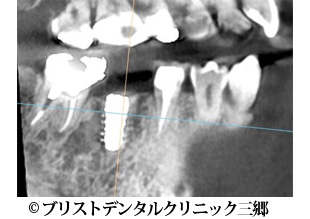

【症例3】インプラント

- 治療前

- 治療後

- 治療名

- インプラント

- 費用

- 450,000円(税込)

- 期間

- 9ヶ月

- 通院頻度

- 約2週間ごと

- 性別・年齢

- 女性 50代

治療内容

-

患者様の症状

右下奥歯が腫れてきて痛みがあり食べれないとのことで当クリニックに来院されました。

レントゲン上で右下の6番目の根の先端に大きい影が見られます。 -

治療法

まず被せ物を外し根の治療を行ったのですが歯根破折が確認できたため抜歯を行いインプラントにて噛み合わせを回復することにしました。

抜歯後半年経ってから骨が回復してくるのを待ちました。 -

治療結果

色合い等大変、満足されていました。また何でも噛めるそうです。

※治療結果は患者様によって個人差があります。

治療を行う上での注意点 (リスク・副作用)

歯磨き不足や定期検診に来られなかったりするとインプラント周囲炎になる可能性がある。

長期による経年劣化により被せ物を交換しなければならない場合がある。